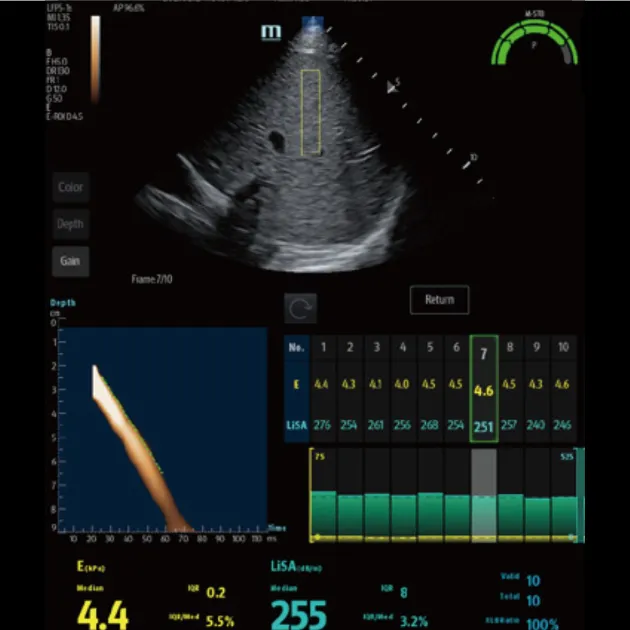

Advanced ViTE (визуализированная транзиторная эластография)

- Проводить количественное выявление и оценку фиброза и стеатоза печени под визуальным контролем 2D-ультразвука в режиме реального времени

- Позволяет избежать образования кровеносных сосудов и повреждений, повысить точность и достоверность измерения

- Значительно снижает сложность операции, повышает точность и повторяемость количественных измерений

Быстрое интеллектуальное получение данных Q-сканирования

- Нажатием одной кнопки можно автоматически и непрерывно получать 10 групп эффективных данных и проводить интеллектуальный анализ

- Точные и достоверные результаты обнаружения могут быть получены немедленно, всего через 7 секунд после позиционирования

Надежный показатель контроля качества

- Индекс давления (P): качественный контроль давления зонда

- Индекс стабильности движения (m-STB): обеспечивает стабильность дыхания

- Четкая индикация с другим цветом для улучшения контроля качества во время обследования